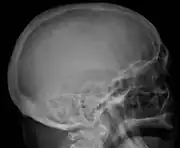

-

Skull X-ray showing multiple lucencies due to multiple myeloma -

Bone pain affects almost 70% of people with multiple myeloma and is the most common symptom.[16] Myeloma bone pain usually involves the spine and ribs, and worsens with activity. Persistent, localized pain may indicate a pathological bone fracture. Involvement of the vertebrae may lead to spinal cord compression or kyphosis. Myeloma bone disease is due to the overexpression of receptor activator for nuclear factor κ B ligand (RANKL) by bone marrow stroma. RANKL activates osteoclasts, which resorb bone. The resultant bone lesions are lytic (cause breakdown) in nature, and are best seen in plain radiographs, which may show "punched-out" resorptive lesions (including the "raindrop" appearance of the skull on radiography). The breakdown of bone also leads to the release of calcium ions into the blood, leading to hypercalcemia and its associated symptoms.

The diagnostic examination of a person with suspected multiple myeloma typically includes a skeletal survey. This is a series of X-rays of the skull, axial skeleton, and proximal long bones. Myeloma activity sometimes appears as "lytic lesions" (with local disappearance of normal bone due to resorption). And on the skull X-ray as "punched-out lesions" (pepper-pot skull). Lesions may also be sclerotic, which is seen as radiodense.[48] Overall, the radiodensity of myeloma is between −30 and 120 Hounsfield units (HU).[49] Magnetic resonance imaging is more sensitive than simple X-rays in the detection of lytic lesions, and may supersede a skeletal survey, especially when vertebral disease is suspected. Occasionally, a CT scan is performed to measure the size of soft-tissue plasmacytomas. Bone scans are typically not of any additional value in the workup of people with myeloma (no new bone formation; lytic lesions not well visualized on bone scan).